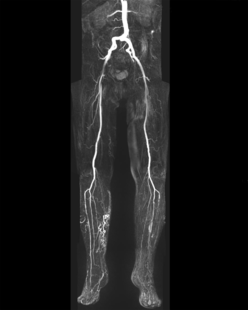

Magnetresonanztomografie:

Die Gefäßdarstellung erfolgt in einem modernen 48-Kanal-Magnetresonanztomografen (Siemens Area 48) der mit spezieller Hard- und Software für die Darstellung aller Gefäße des Körpers ausgerüstet ist. Dazu wird überwiegend ein gadoliniumhaltiges Kontrastmittel verwendet, welches meist über eine Armvene injiziert wird. Die Untersuchung dauert ca. 10 – 20 Minuten.

Neben der Erfassung von Veränderungen des Gefäßdurchmessers zur Beurteilung der Durchblutungsstörung, liefert uns diese Untersuchungsform auch wichtige Information zum Aufbau der Gefäßwände, zum Beispiel bei entzündlichen Gefäßerkrankungen und zum Nachweis von durchblutungsgestörtem Gewebe.

Für Patienten die aufgrund von Erkrankungen kein Kontrastmittel verabreicht bekommen dürfen, besteht durch eine spezielle softwaregestützte Untersuchungsmethode die Möglichkeit, eine Angiografie der Beine auch ohne Kontrastmittelgabe durchzuführen.